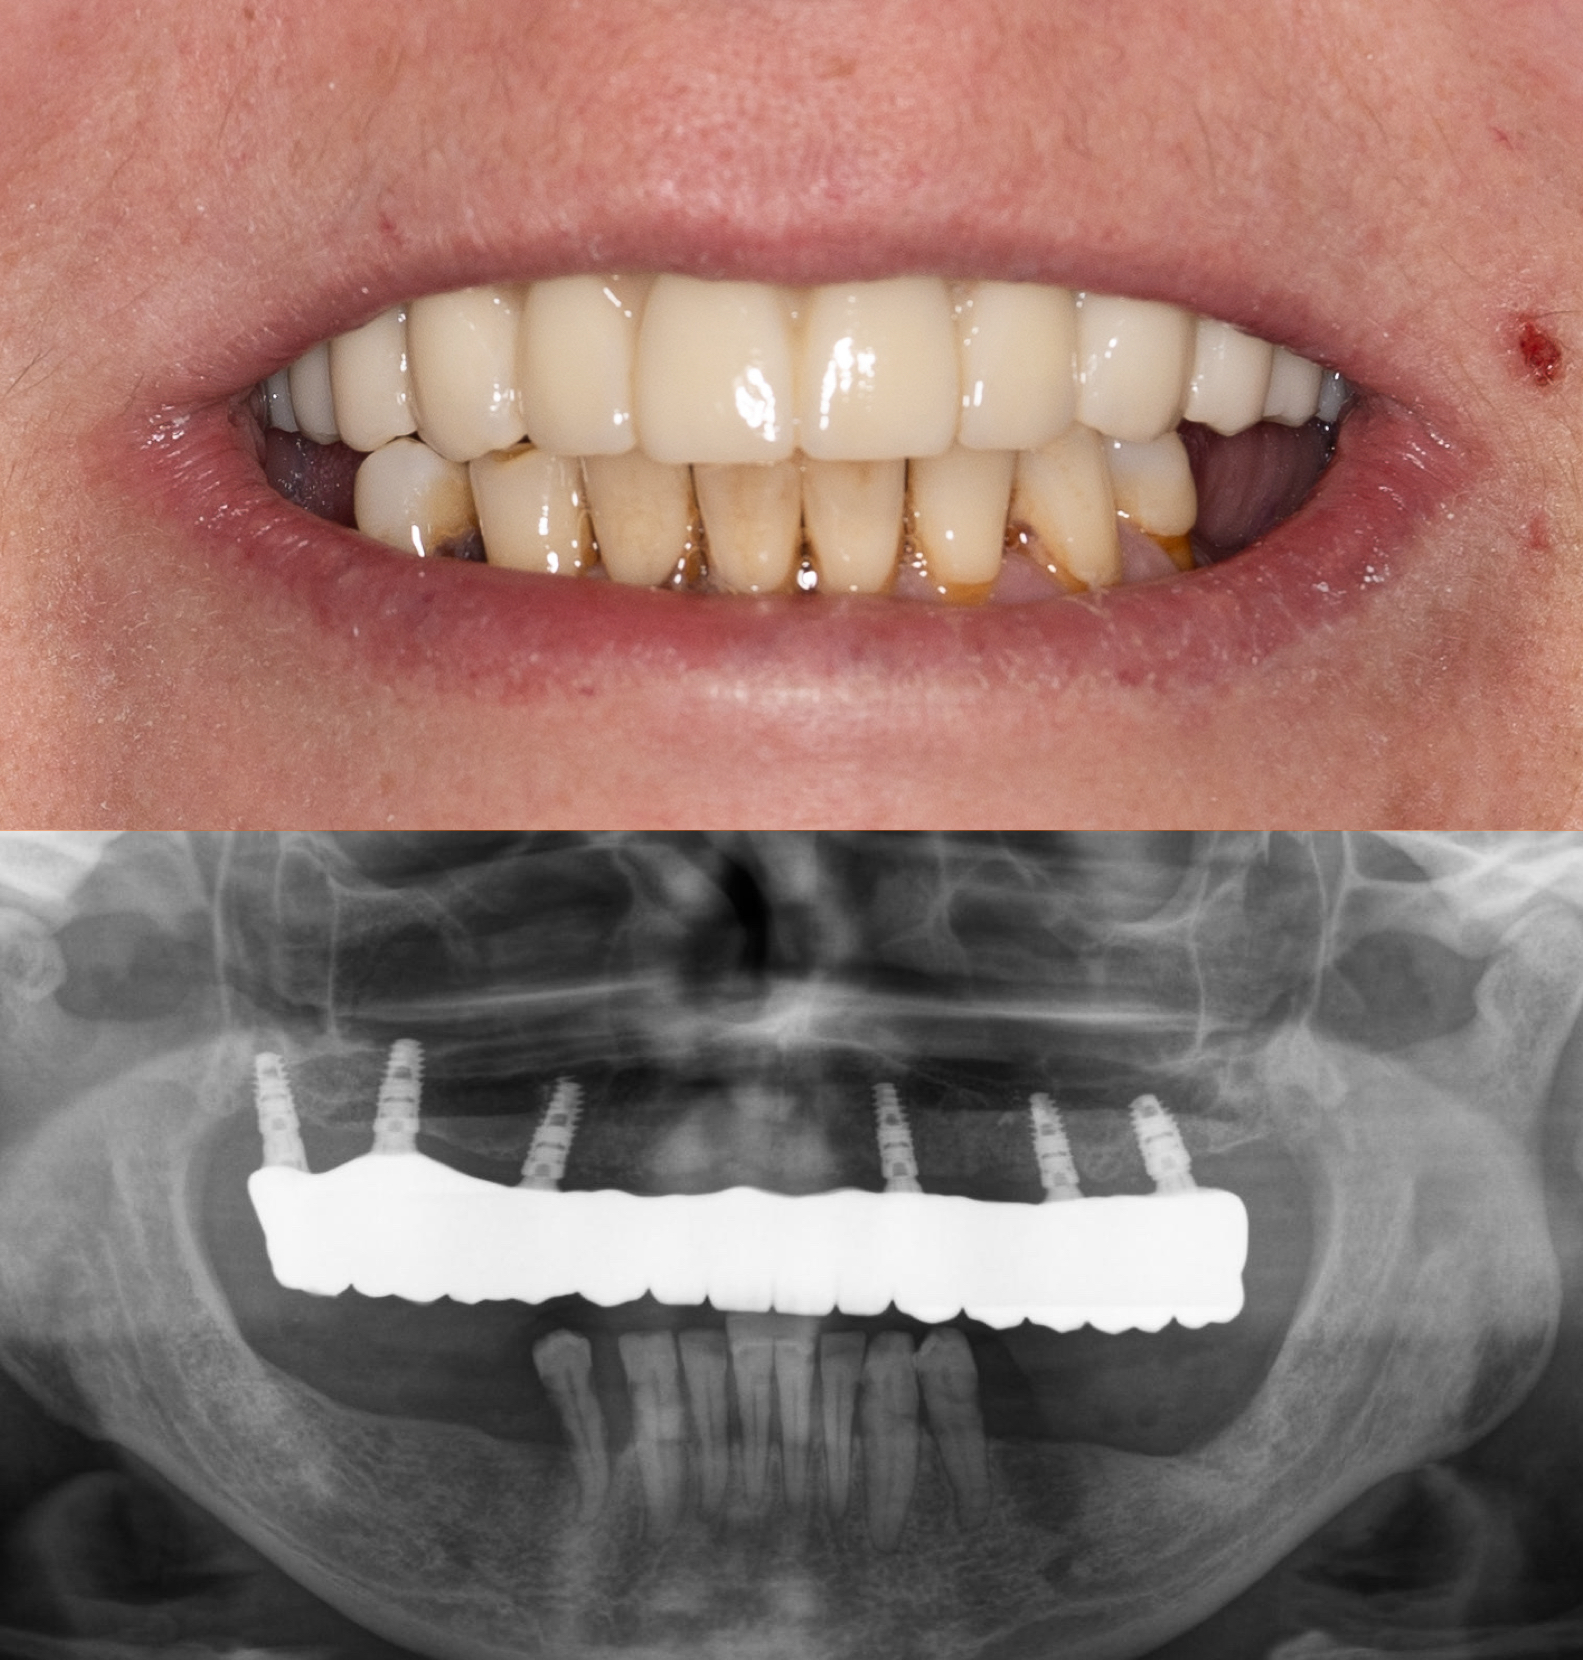

Przypadek 1

Pacjent zgłosił się z powodu licznych problemów z zębami oraz dolegliwości bólowych głowy. Zęby z powodu znacznej ruchomości nie stanowiły odpowiedniej podpory podczas żucia. Niestety wieloletniej terapia periodontologiczna choroby przyzębia nie przynosiła efektów. Zęby zostały zakwalifikowane do usunięcia. Nowy zgryz został odtworzony i oparty na 6 implantach w szczęce oraz 5 w żuchwie. Informacje z badania stawowe "kondylografii" pomogły zaplanować nowe prawidłowe zwarcie. Poza wyleczeniem dolegliwośći bólowych głowy oraz przywróceniu komfortu żucia i uśmiechu, Pacjent po zakończonej terapii zgłasza znaczne ograniczenie chrapania.

leczenie zaplanował oraz przeprowadził lek. dent Kamil Kikowicz